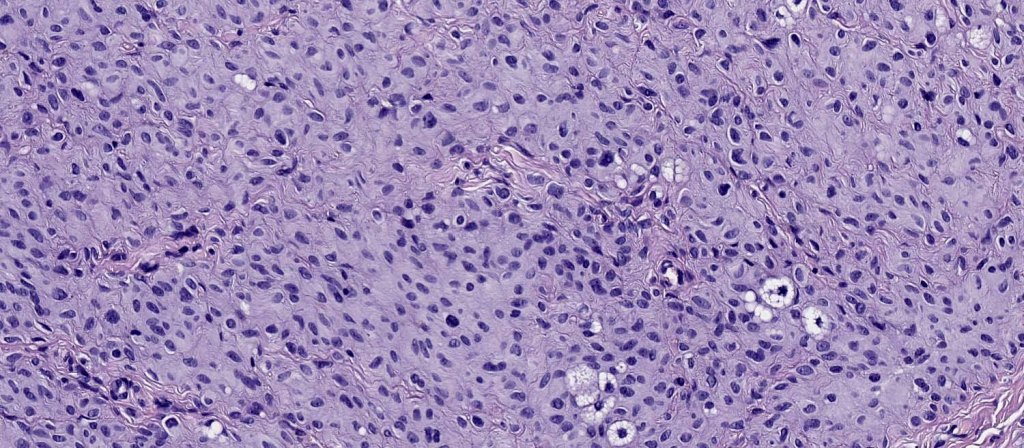

.Balloon cell change is most often seen in banal melanocytic nevi but it has also rarely been described in cellular blue nevus, dysplastic nevus, combined nevus, halo nevus & Spitz nevus. Lesions with <50% of balloon cells are sometimes described as nevi with balloon cells. Nevi with >50% balloon cells are described as balloon cell nevus.

.Balloon cell nevs genrally has uniform, hyperchromatic nuceli (as opposed to the vesicular nuclei with prominent nucleoli) seen in melanoma. Mitoses are absent.(In my experience, balloon cell melanoma is more common than balloon cell nevus).

The importance of the entity is that it must always be distinguished from balloon cell melanoma. All cases should be scrutinized very carefully for pleomorphism and mitotic activiy before rendering a diagnosis of balloon cell nevus.